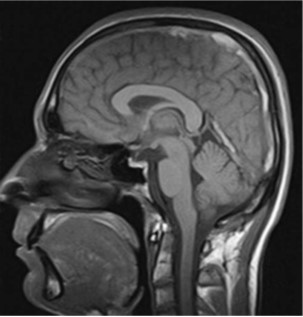

Question: A 23-year-old female presents to the clinic for evaluation of a headache. She is currently 14 weeks pregnant. She complains of a holocephalic headache for the last week, which is worsening in intensity. The headache is worse at night and causes blurry vision.Her neurological examination is remarkable for bilateral papilledema. The sagittal T1 magnetic resonance image (MRI) is shown here. Which of the following is the most likely diagnosis?

Explaination: Pregnant patients are at higher risk of VST because pregnancy creates a hypercoagulable state often worsened by dehydration. MRI and magnetic resonance venography are the first-line tests for determining whether there is a VST because both can be done without contrast. The provided image is a non-contrast T1-weighted image. This demonstrates a hyperintense T1 signal in the sagittal sinus and the great vein of Galen, which is consistent with an acute VST.